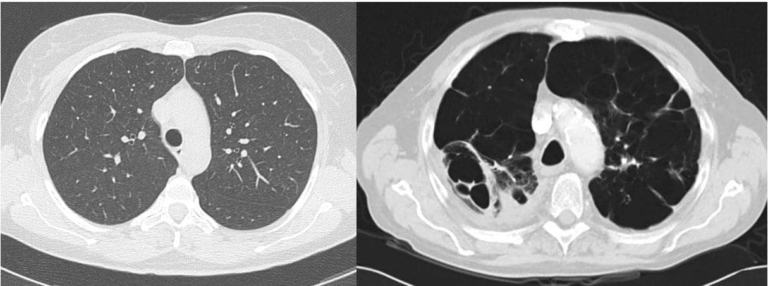

胸部X線またはCTスキャン

医師は COPD と肺気腫を診断するためにX 線とコンピューター断層撮影(CT) スキャンを使用することがあります。これらの画像検査では、がんや肺瘢痕の一種である肺線維症などの他の問題も特定できます。